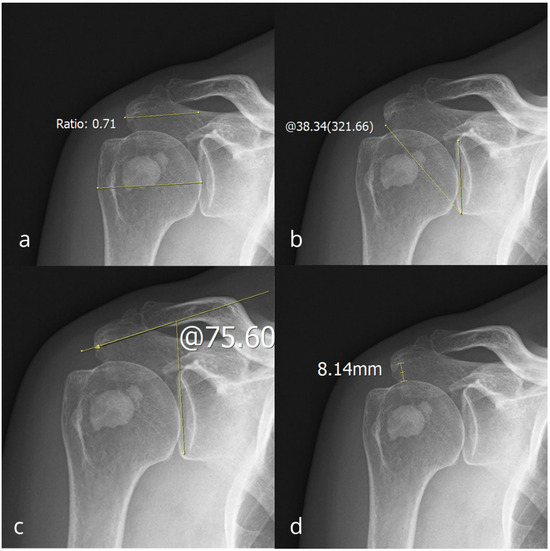

Association Between Osseous Shoulder Morphology and Pathoanatomical Characteristics of Calcific Deposits in Rotator Cuff Calcific Tendinitis

Background/Objectives: Rotator cuff calcific tendinitis (RCCT) is a common cause of shoulder pain. The role of acromial morphology in RCCT pathogenesis remains unclear. This study aimed to evaluate association between acromial morphological parameters and calcific deposit characteristics in patients with RCCT. Methods: We [...] Read more.